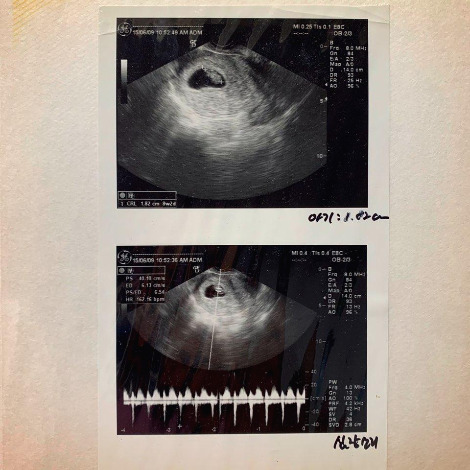

그 주 토요일 쿠리와 나는 산부인과에 갔다. 여의사 선생님을 찾아갔는데 선생님은 우리에게 아이는 꼭 낳아야 한다고 했던 것 같다. 검진을 하는데 일부러인지 원래 그런지는 모르겠지만 심장소리를 들려주셨다. 한 달도 안된 콩만 한 아기 심장소리는 정말 컸다. 매우 규칙적이고 또렷한 소리였다.

저 작은 콩은 쿠리와 내 인생을 완전히 바꿔놓았다. 하하하.

그 심장소리를 듣고도 다른 생각을 할 수 있는 사람이 있을까? 많지 않으리라 생각한다.